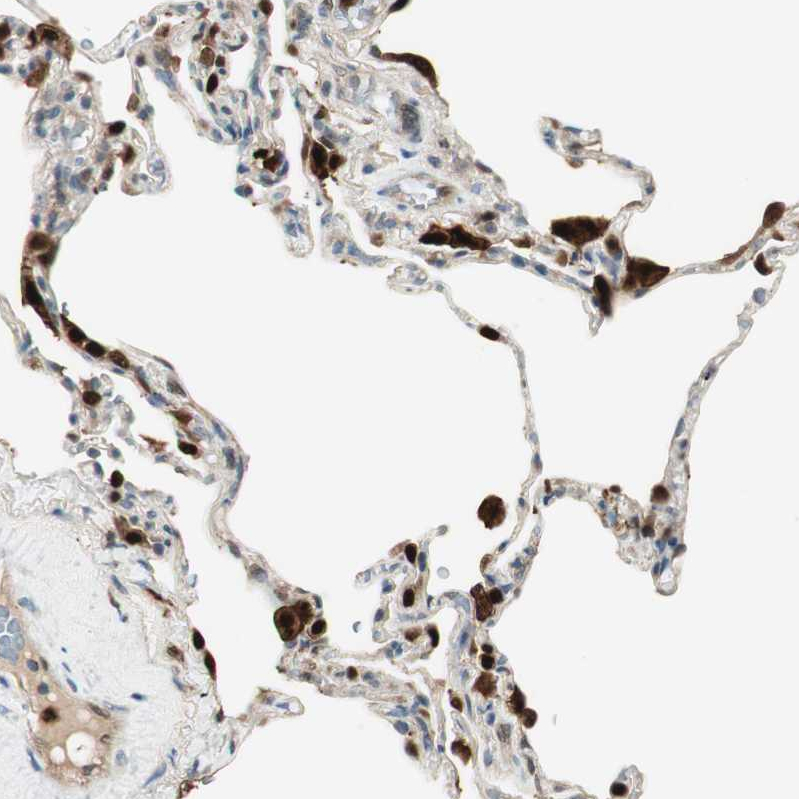

Immunohistochemical staining of human lung shows strong cytoplasmic and nuclear positivity in macrophages.